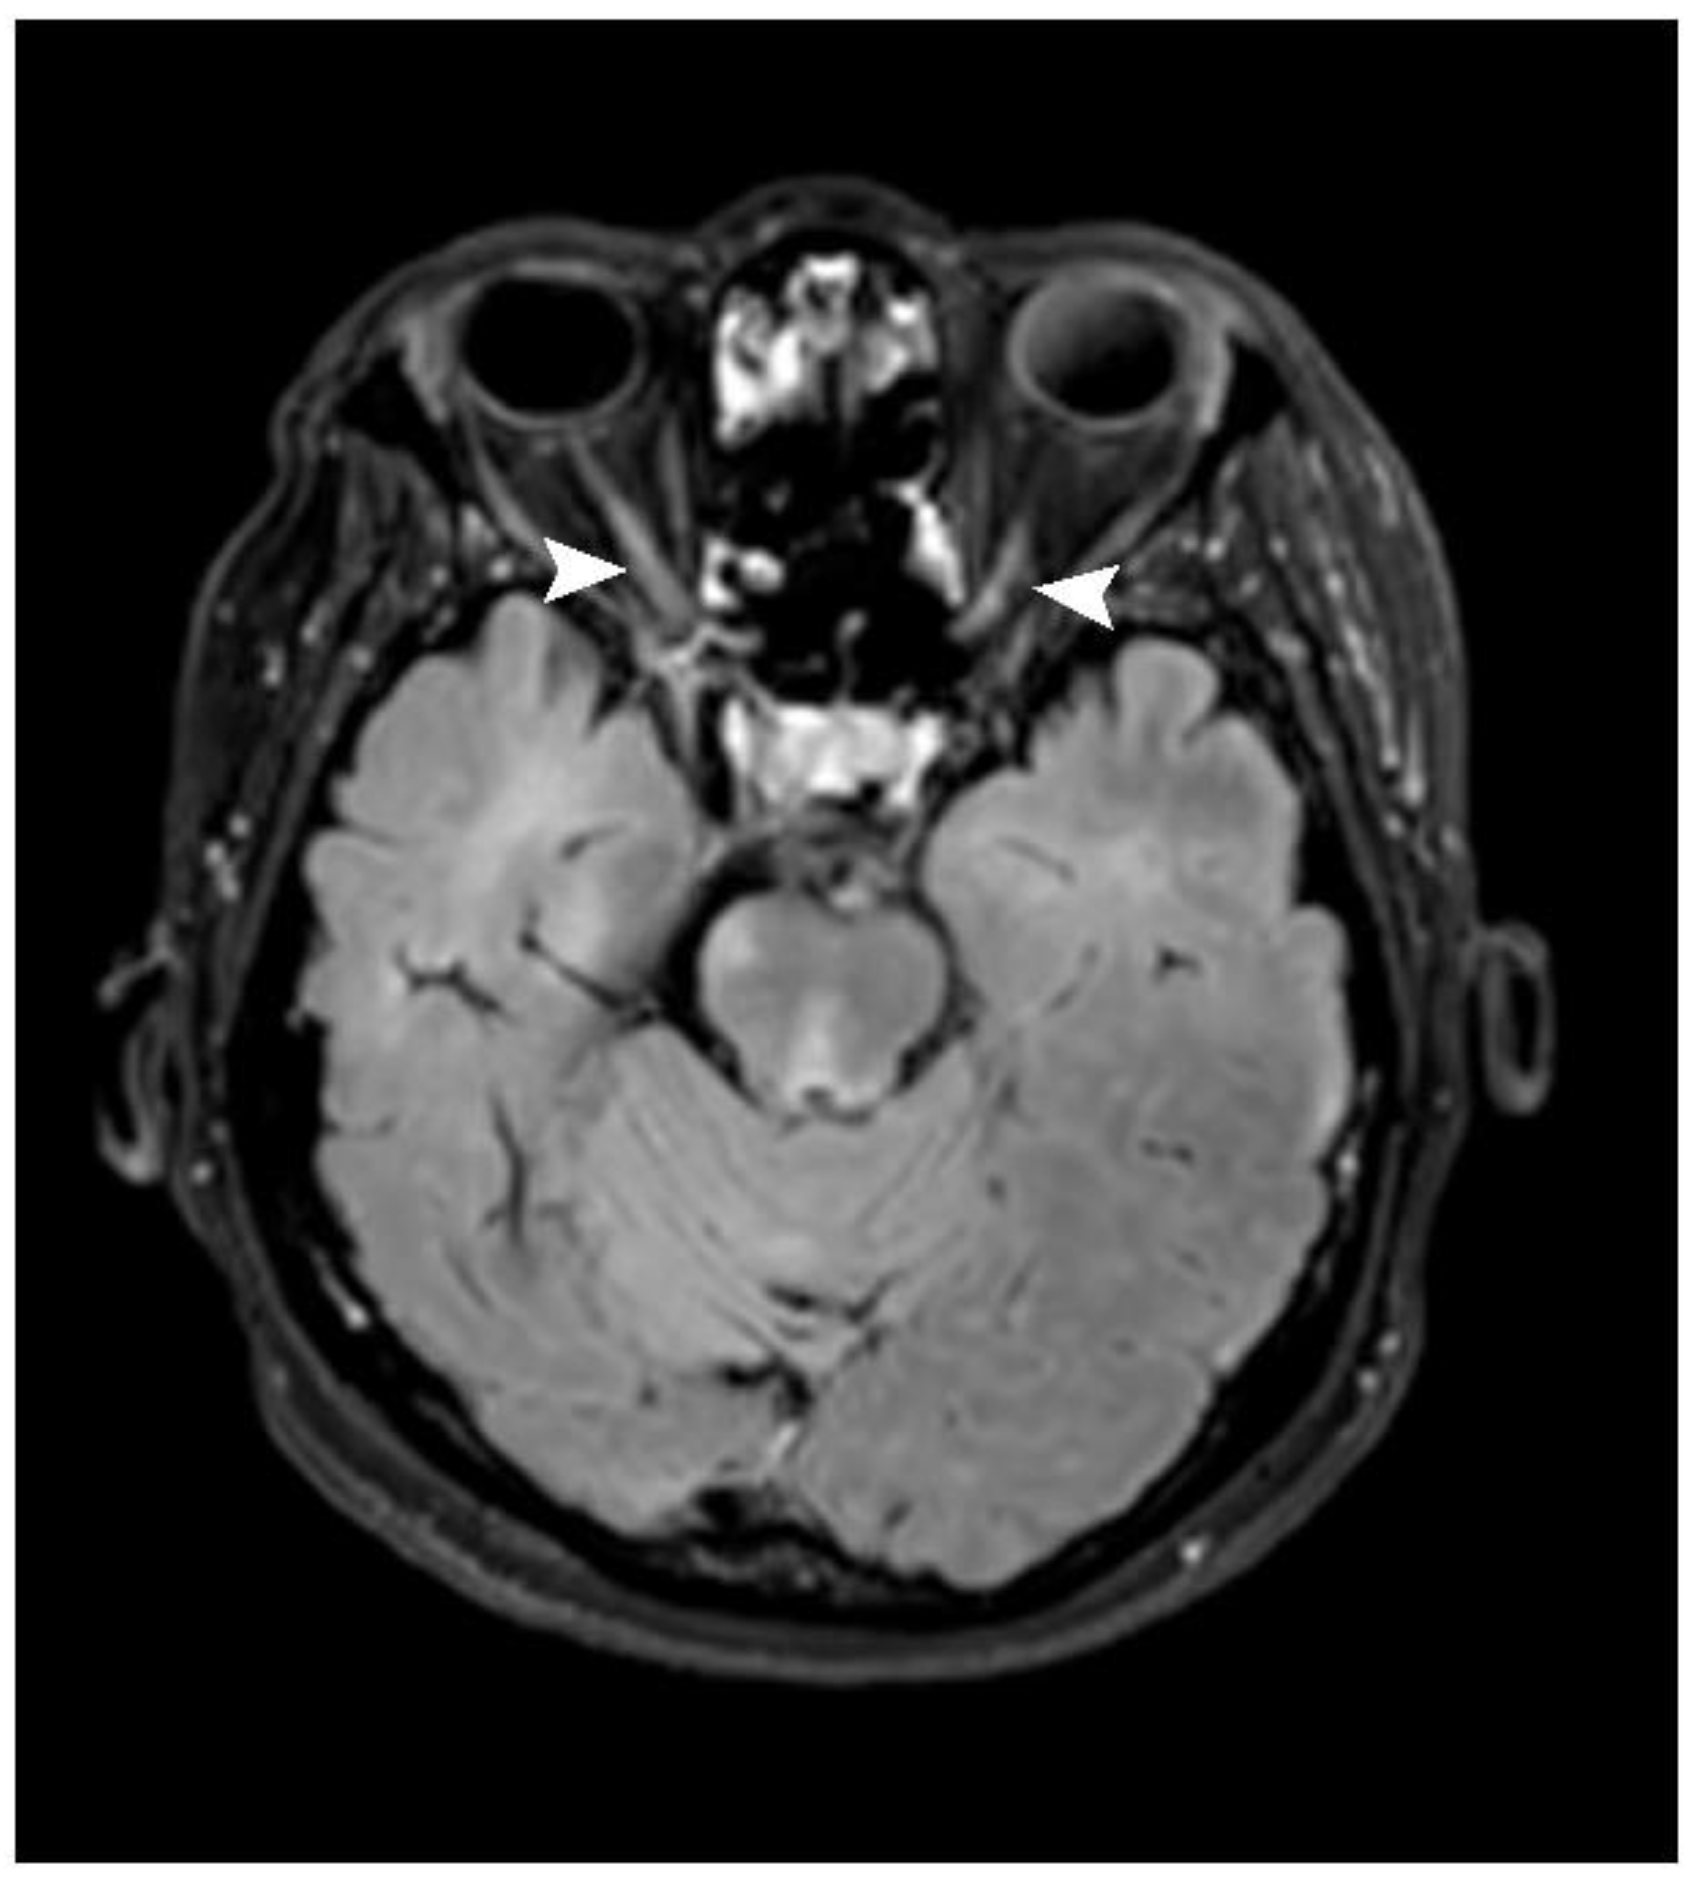

Figure 6. Axial post-contrast FLAIR image shows patchy enhancement at posterior halves of bilateral optic nerves (arrowhead) in keeping with bilateral optic neuritis.

Optic nerve lesions were identified in seven patients (21.9%). A unilateral lesion and bilateral lesions were found in three and four patients (42.9 and 57.1%), respectively. A long-segment lesion (longer than 50% of the optic nerve length) was identified in only one patient, while the remainder showed short-segment lesions (six patients, 85.7%). Of these, four showed posterior-half lesions (66.7%; Figure 6, Table 2).